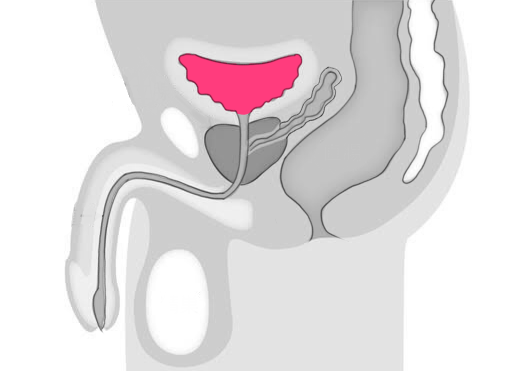

膀胱は尿を一時的に貯める器官であり、このがんは膀胱の内側の細胞が異常に増殖することで発生します。

末期の膀胱がんは、膀胱の壁を突き破り、隣接する臓器やリンパ節、遠隔の臓器へと転移してしまうことが特徴です。

さらに、膀胱がんが進行すると、尿道や直腸、子宮などの近隣の臓器に影響を及ぼすことがあります。